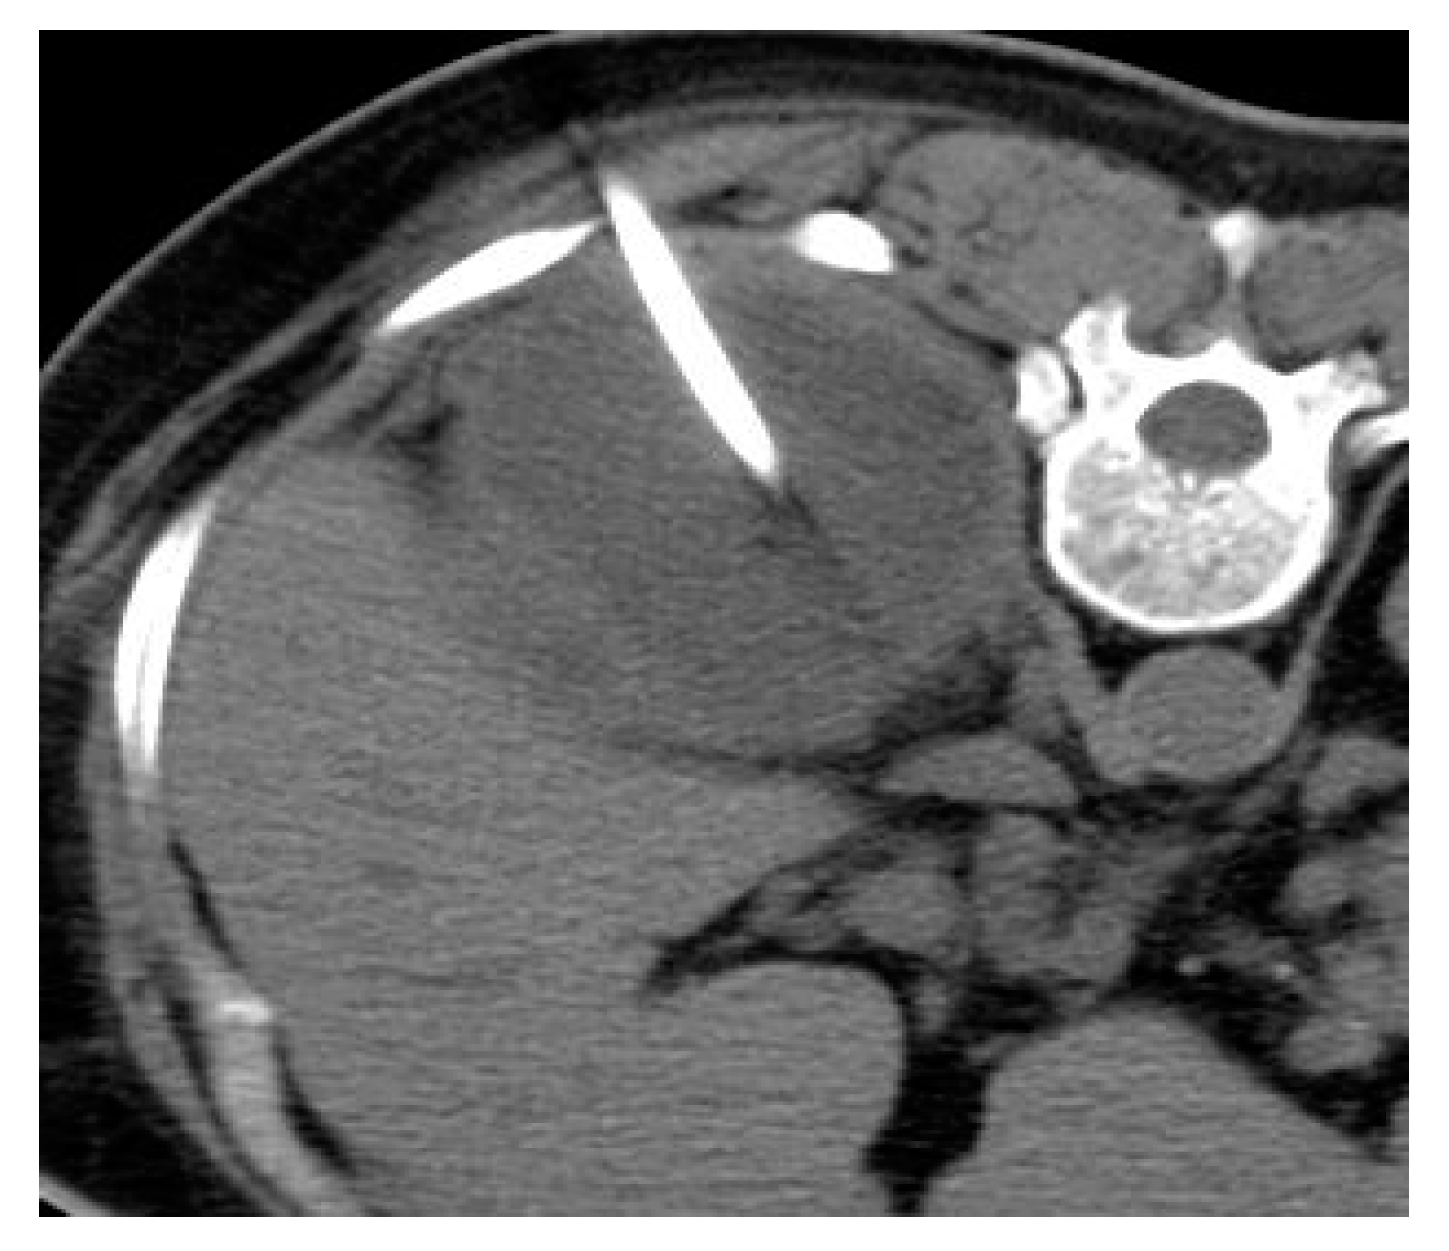

2.5. Xanthogranulomatous Pyelonephritis (XGP)

| Xanthogranulomatous Pyelonephritis | Non-functioning enlarged kidney, obstructing stone within a non-dilated renal pelvis, expansion of the calyces, and inflammatory changes in the perinephric fat. |